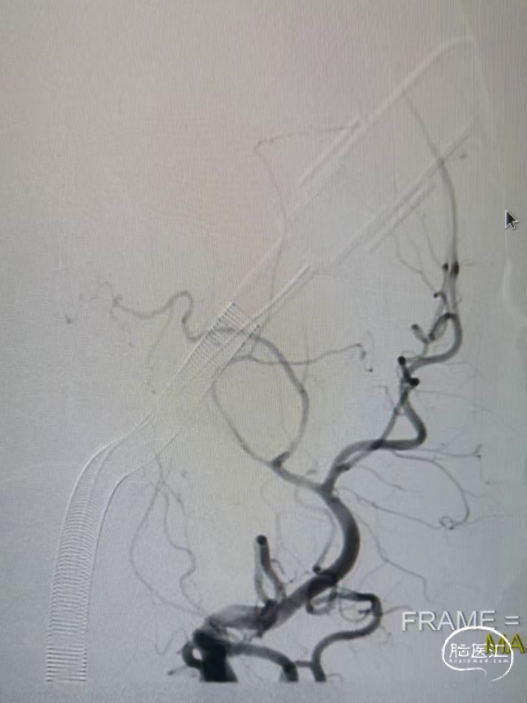

造影显示左侧的颈内动脉末端闭塞,中间导管造影显示大脑前和大脑中动脉显影,明确颈内末端闭塞。

中间导管到位之后送入RECO取栓支架 6*30cm、微导管,调整好微导管位置之后释放RECO取栓支架 6*30cm,支架展开之后血管血流通畅。

先负压抽吸,然后释放RECO取栓支架 6*30cm在负压下进行取栓操作。

➢术后即刻影像

术后颈内动脉末端血流通常,左侧大脑前动脉和大脑中动脉显影正常。